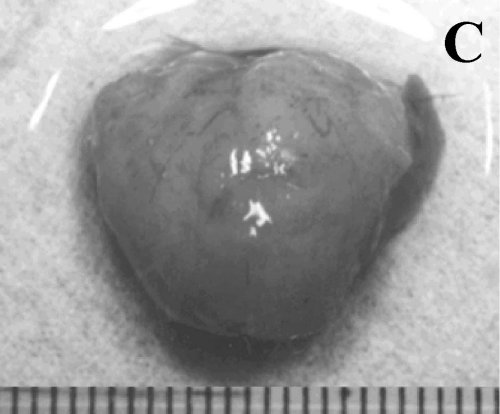

Figure 1. A subcutaneously

implanted hamster. A. Appearance before tumor resection. B.

Panoramic view after resection. C. Resected specimen without the

covering skin. D. Histopathologic view

showing a moderately differentiated adenocarcinoma (H&E, 200x). |

Success

rate of Implantation, Appearance of Resected Tumors and Survival Time

All 35 animals developed tumors at

the site of implantation, palpable after one week. At the time of resection,

the diameter of the tumor ranged between 18 and 22 mm. Five hamsters in the STI

group, but none in the SCI group, showed adhesion to deep tissue. The skin

covering the tumor was adhered in all animals of both groups. All tumors showed

a well-circumscribed surrounding capsule. Some necrosis was found in the center

of all tumors in the SCI group, and in the center and periphery of all tumors

in the STI group. All resected specimens were confirmed histologically as

moderately differentiated adenocarcinoma. However, tumors of the STI group

consisted of more connective tissue, as shown in Figure 1. Thus, the success

rate of implantation was 100%. The mean survival time in the SCI group was 151±